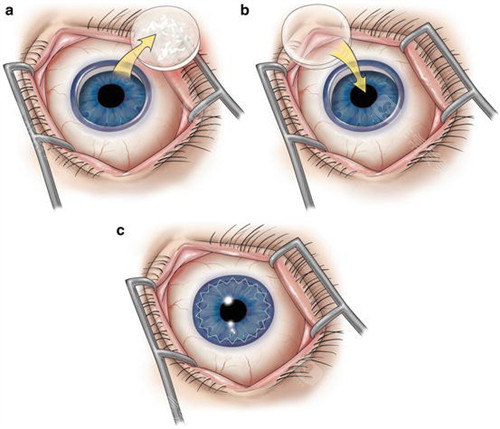

板层角膜移植:2万元起/单眼

适用人群:角膜浅层病变(如瘢痕、营养不良)

技术亮点:保留健康内皮层,排斥率≤5%,1个月即可拆线

穿透性角膜移植:4.5万元起/单眼

适用人群:全层混浊或穿孔(如化学伤、溃疡)

含金量:飞秒激光辅助切口(精度0.1mm),术后散光降低40%

角膜内皮移植:3万元起/单眼

黑科技:3mm微切口植入,无需缝合,术后次日可视物,适合大泡性角膜病变